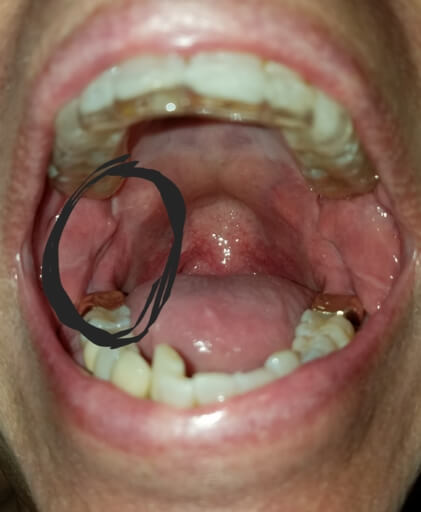

Hi, I have a frenulum on the right side of my mouth. It connects to my gums about 1cm behind the upper and lower back molars. It has become tight and painful. Have you ever seen anything like this? Is it safe to have it cut? I will attempt to add a photo. Thank you, H. Jay Graber

A frenum or frenulum is a small fold of tissue that restricts and secures the motion of a mobile organ.  I have not heard of a frenulum in the back of the mouth. It would be best to bring this to the attention of your dentist, especially because it is causing discomfort.  I did not see a picture attached to your question, however I am wondering if it is part of your cheek or possibly an impacted tooth that may be causing this discomfort.  Use warm salt water rinses several times a day to soothe the tissues until you have a proper exam and diagnosis.

A frenulum or frenum is a small fold of tissue that restricts or secures the motion of a mobile organ.  I have not seen a fold of tissue (unless sutured) that connects distal to the molars.  There is a frenum that connects your tongue to the floor of your mouth as well as one that attaches your lips to your jaws.  Since you are experiencing pain, it is important for you to see your dentist immediately to be sure you do not have an infection or a tooth that is creating swelling in the area.